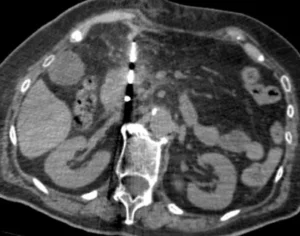

Il cancro del pancreas è una patologia che si sviluppa a partire da cellule anomale nel tessuto pancreatico. Il pancreas, situato nell’addome dietro lo stomaco, è un organo fondamentale per la digestione e il controllo dei livelli di zucchero nel sangue. Esso è composto da due principali sezioni: il pancreas esocrino, che produce enzimi digestivi destinati all’apparato gastrointestinale, e il pancreas endocrino, che secerne insulina e glucagone, ormoni essenziali per la regolazione della glicemia.

In oltre l’80% dei casi, i tumori pancreatici si originano nel pancreas esocrino, che gioca un ruolo cruciale nella digestione dei nutrienti. Questi tumori si sviluppano principalmente nella testa o nel collo del pancreas (circa il 75% dei casi), mentre una percentuale inferiore riguarda il corpo (15-20%) e la coda (5-10%) dell’organo.

Il pancreas è diviso in tre sezioni: testa, corpo e coda. Queste aree sono tutte situate nell’addome, vicino a organi vitali come lo stomaco, l’intestino e il fegato. La comprensione della localizzazione del tumore è cruciale per la diagnosi e il trattamento, in quanto influisce sulle scelte terapeutiche, come la chirurgia o le tecniche di radiologia interventistica per il trattamento dei tumori avanzati.